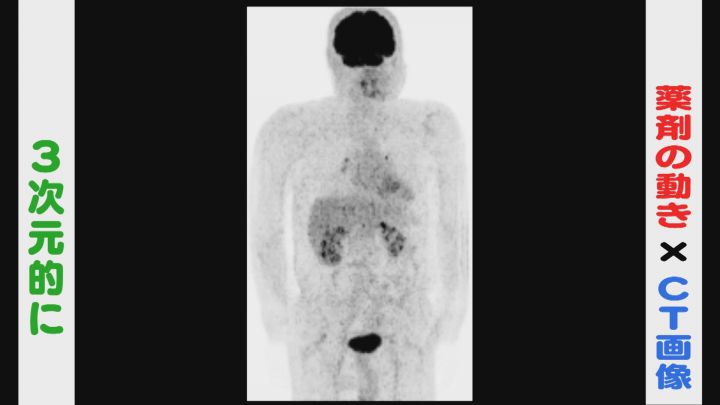

「PET検査」とは、がん細胞が正常の細胞に比べ「多くのブドウ糖を取り込む」という性質を利用して、ブドウ糖を含む薬剤を体内に投与し、専用の機械で撮影します。

この薬が多く集まる場所を突き止めて、体内に潜むがんを見つけ出すということです。

海外で開発された「PET-CT」は、ブドウ糖を含む薬剤の動きとCTスキャンを組み合わせ、がんの位置や大きさを三次元的に探ることができます。

岩田理事長によると頭から膝まで全身が一度にわかり、小さながんを発見するのに優れています。